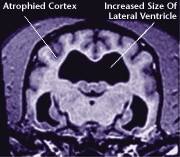

![]() Healthy Older Brain | ![]() Older Brain with Damage |

| MRI scans show loss of brain tissue in affected dogs. Note: MRI scans are not harmful to dogs. | |